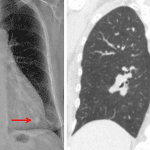

- 10 mm nodule in the left lower lobe

- Lung nodule

10 mm nodule in the left lower lobe. Recommend nonemergent chest CT for further evaluation.